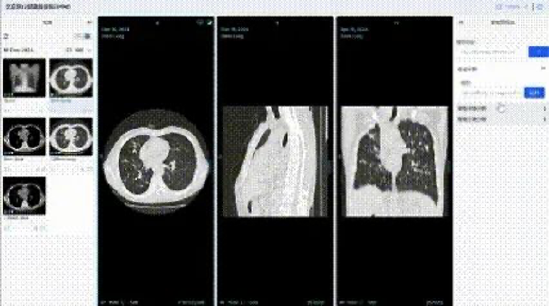

中国联通联合国内多家顶尖医疗机构,构建了覆盖影像、诊疗、药品等全维度的高质量数据集,其中,数据集总规模达100TB,胸部CT影像数据集标注2万余例,肺结核辅助诊断模型准确率超95%;耳部CT影像数据集标注5000余例,听觉障碍识别准确率达95%;肾脏病慢病管理数据集整合1万例患者全周期数据,风险预警模型准确率突破95%;药品说明书数据集涵盖58000份药品信息,实现用药风险智能解析与动态评估。

在数据治理与管理方面,联通数智公司构建医疗健康行业可信空间,制定数据脱敏规范,运用数据沙箱和隐私计算双引擎处理数据,确保“原始数据不出域、数据可用不可见”。建立11项数据治理全流程运营标准,通过多维度举措保障数据质量与安全。例如,在胸部CT影像数据标注中,采用双盲标注和专家抽样审核,确保标注一致性评估结果超95%,准确性达98%以上。

基于该高质量数据集,中国联通研发了一系列医疗专科智能体。基于胸部CT影像的肺结核疾病筛查与诊断模型智能体,准确率超 95%,可实现分钟级快速检测;肾脏病慢病管理干预模型智能体、耳部疾病辅助诊断模型智能体,助力医务人员提高诊断效率及诊疗方案准确性;药品全生命周期智能评估模型智能体,为药品研发、监管等提供全链条数据支撑。